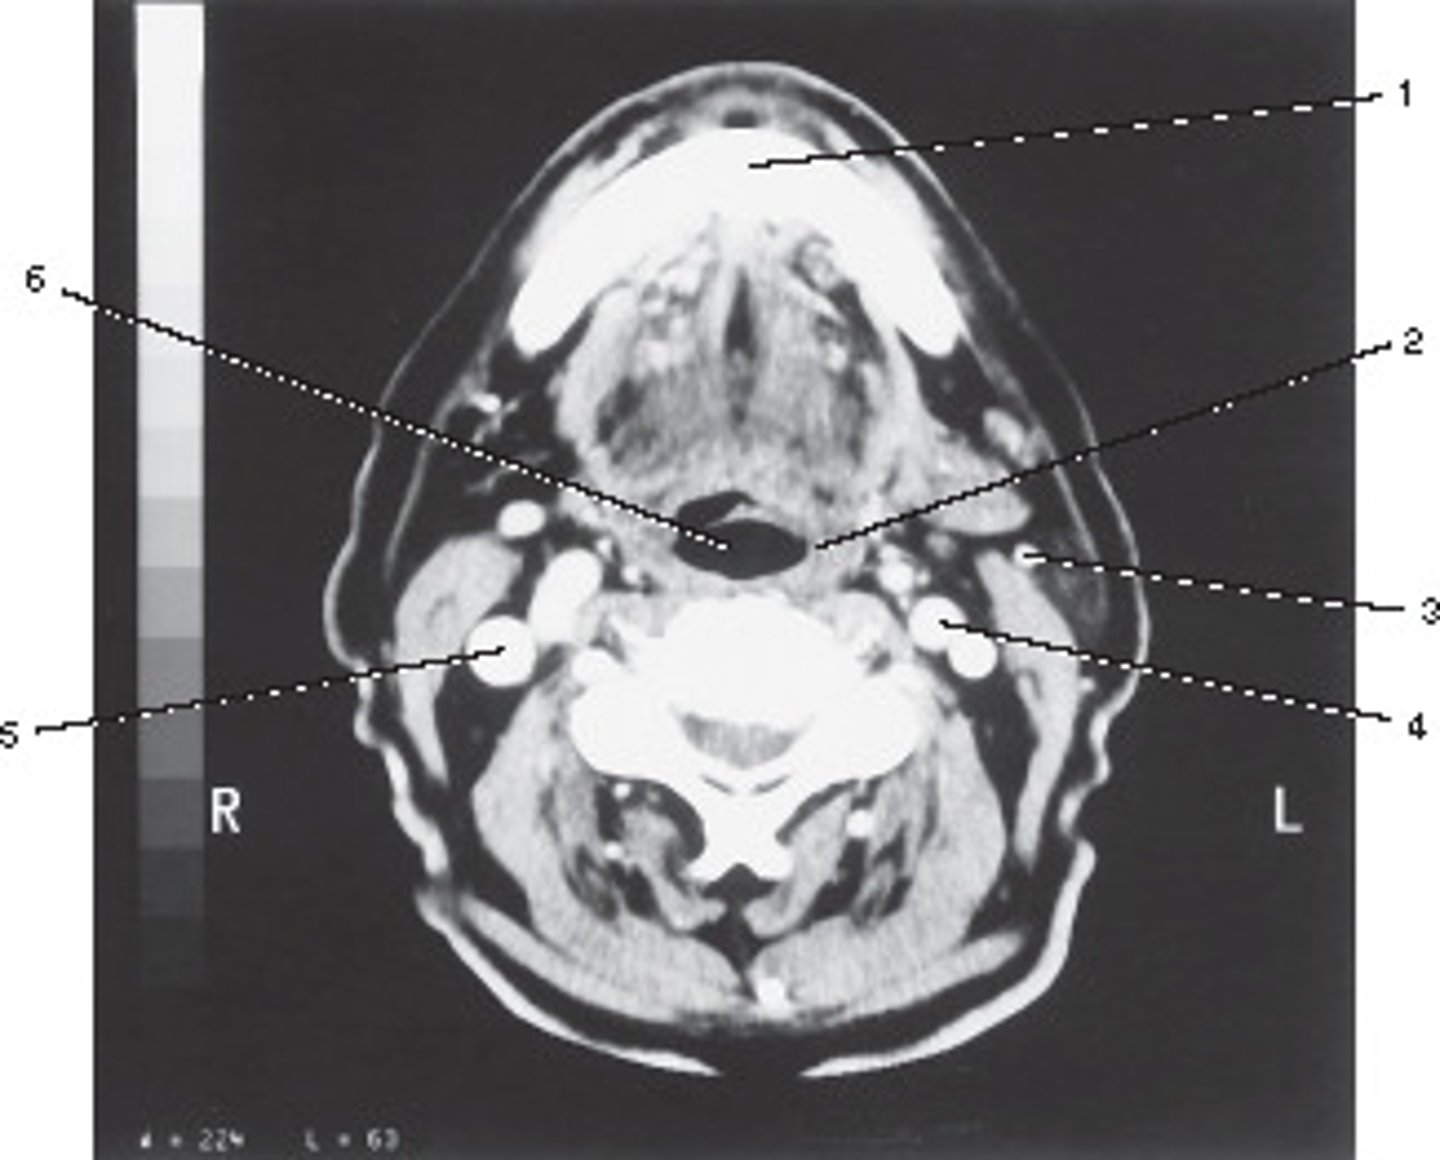

Oropharynx

Number 6 corresponds to which of the following?

<p>Number 6 corresponds to which of the following?</p>

Common Carotid Artery

Number 5 corresponds to which of the following?

<p>Number 5 corresponds to which of the following?</p>

Retromandibular Vein

Number 3 corresponds to which of the following?

<p>Number 3 corresponds to which of the following?</p>

Vertebral Artery